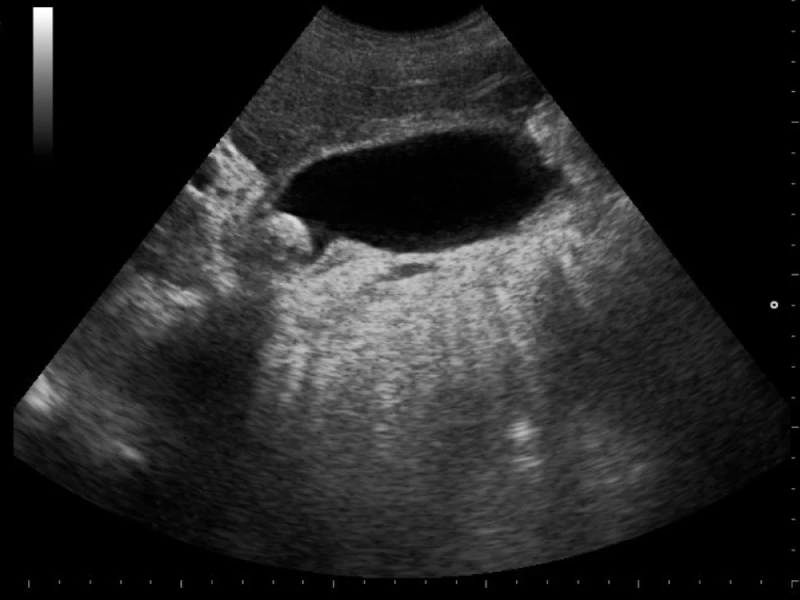

Torsión de testiculo

Torsión de testiculo en ecografia Presentación Edad: N/A Género: Femenino Discusión Artículos